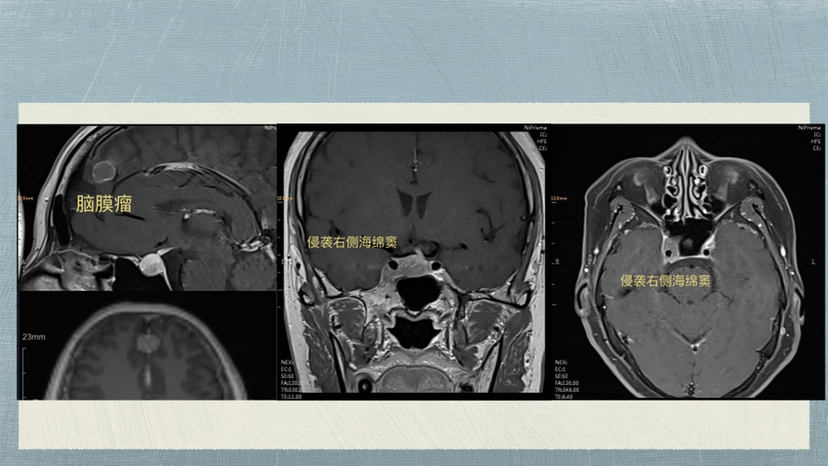

“侵袭性垂体腺瘤合并大脑镰脑膜瘤”病例 (神经内镜下切除垂体瘤,显微镜下切除脑膜瘤)

脑肿瘤-脑膜瘤

脑肿瘤-垂体瘤

脑膜瘤

垂体瘤

垂体腺瘤